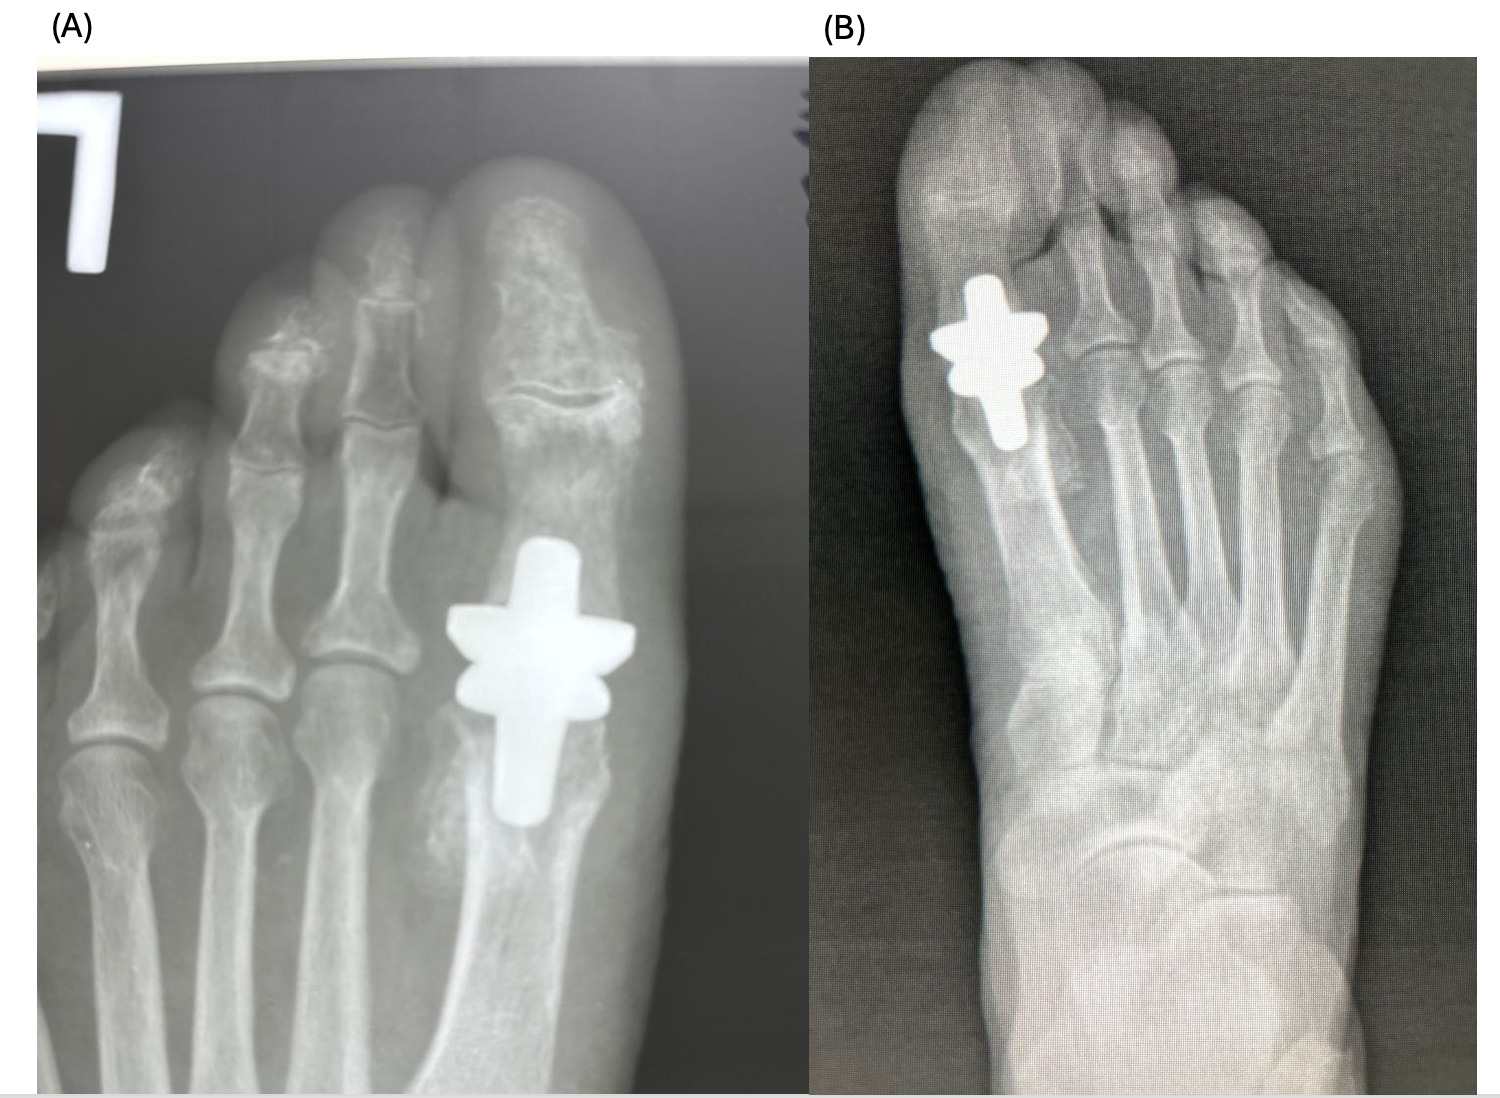

Case #3 (R.A.)

A 58-year-old female patient with a history of arthrodesis of left foot midfoot in 2021, and minimally invasive surgery of the right foot in 2024. The patient had complaints of decreased range of motion and pain on movement of the left foot for the last 5 years. Patient reports worsening after trauma (fall) 7 days ago, since when edema of the left foot appeared, and pain became constant with no response to painkillers. Physical examination revealed crepitus on movement of the first MTP joint and almost no movement (Figure 3 A).

2 and 6 months after the procedure, the patient reports no pain of any type of movement in the joint and improvement in the mobility of the first MTP (Figure 3 B).

The patients had undergone radiographic evaluation of the MTP joint before the surgery, right after surgery, and 2 and 6 months after surgery (Figures 4-9). The radiographic imaging after the surgery confirmed the correct positioning and alignment. At the follow-up, the radiographic images were done to analyze the early healing process, to observe if there were any signs of implant loosening. 2 months after the surgery, no patient had periprosthetic radiolucencies, no stress-related changes. 6 months after surgery, no osteolysis, no migration of the implant.

This case series demonstrates successful short-term results following total first metatarsophalangeal (MTP) joint replacement using ceramic implants in patients with hallux rigidus. All three patients presented significant improvement in AOFAS scores within 2 months postoperatively, with preserved improvement at 6 months. Notably, Patient C, who had the lowest preoperative score (27/100), achieved the greatest relative improvement, reaching 92/100 at 2 months and 89/100 at 6 months. These functional outcomes were confirmed by physical examination findings, with clear improvements in joint alignment and reduction in deformity (Figure 1-3, (B, C)). Moreover, radiographic imaging revealed no signs of complications such as implant loosening, migration or stress-related changes.